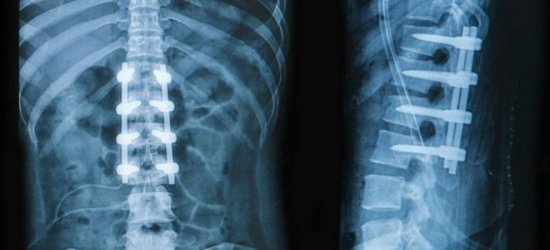

- Рентгенография – определяет патологии, локализованные в костной системе.

Почему болит низ спины, может установить только врач. Ни в коем случае не следует заниматься самодиагностикой и самолечением. Диагноз ставится на основании жалоб больного, клинических проявлений, анамнестических данных, результатов инструментальных методов исследования. Пациенту назначают рентгенографию, миелографию, МРТ, КТ и другие виды обследований.

Компьютерная томография является эффективным и высокоинформативным способом выявления различных структурных изменений в позвоночнике, вызванных травматизацией, инфекционным процессом, опухолевыми образованиями, остеопорозом и другими заболеваниями. В основе миелографии лежит применение контрастирующего вещества. Метод применяют при подозрении на стеноз позвоночного канала, грыжевых образованиях, опухолях и других патологических процессах в позвоночнике.

Неотъемлемая составляющая диагностики болей в спине – инструментальные исследования